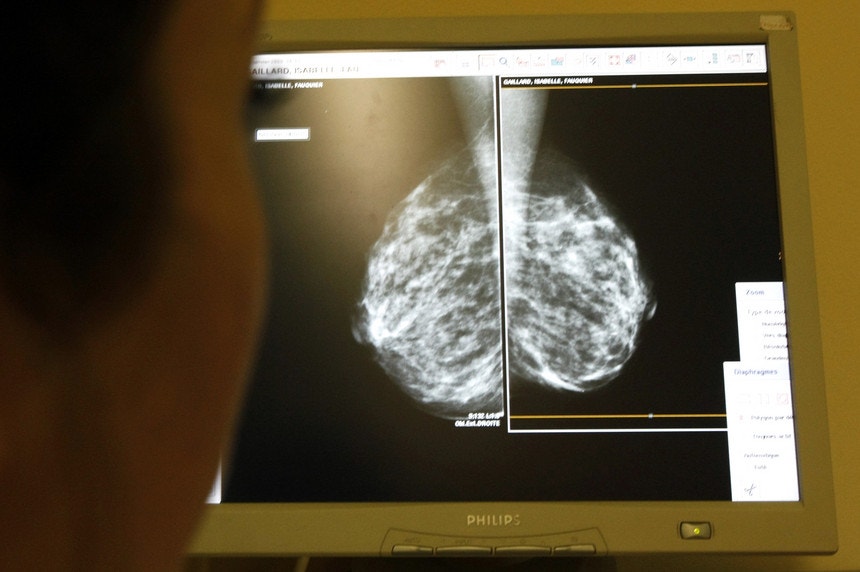

Cancro da mama. Novo teste de saliva deteta risco da doença

O risco de cancro da mama já pode ser detetado com um novo teste de saliva. O teste ainda não foi aprovado pelas autoridades do medicamento e permanece na fase de ensaios clínicos a nível internacional. Em Portugal, esses ensaios decorrem no Hospital de Santa Maria, em Lisboa.